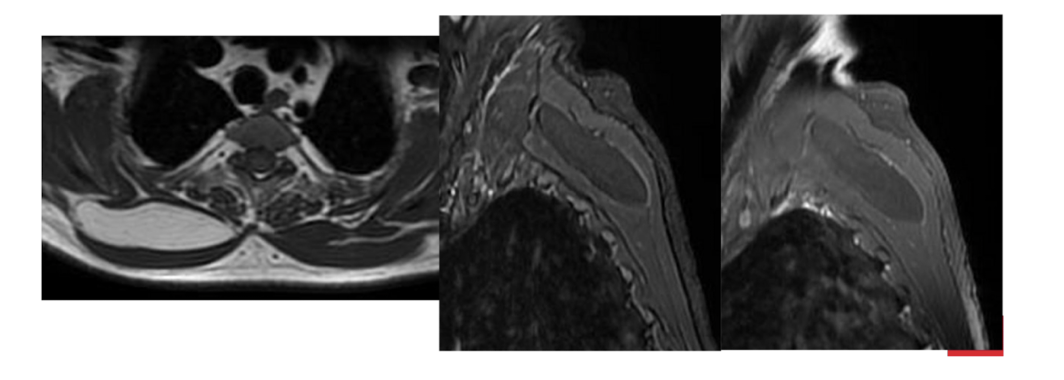

What are the sequences and what is the pathology?

• T1, STIR, T1FS C+

• Tissue lipoma- benign tumour made of fat tissue